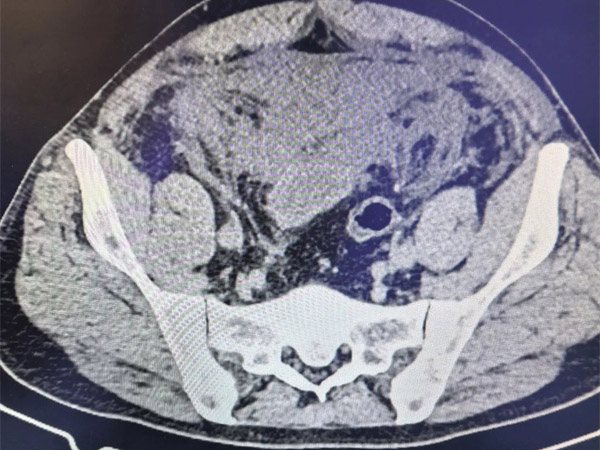

一场突如其来的意外,一次惊心动魄的救援。...